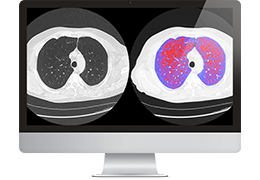

ART-Plan™ Artificial Intelligence Contouring